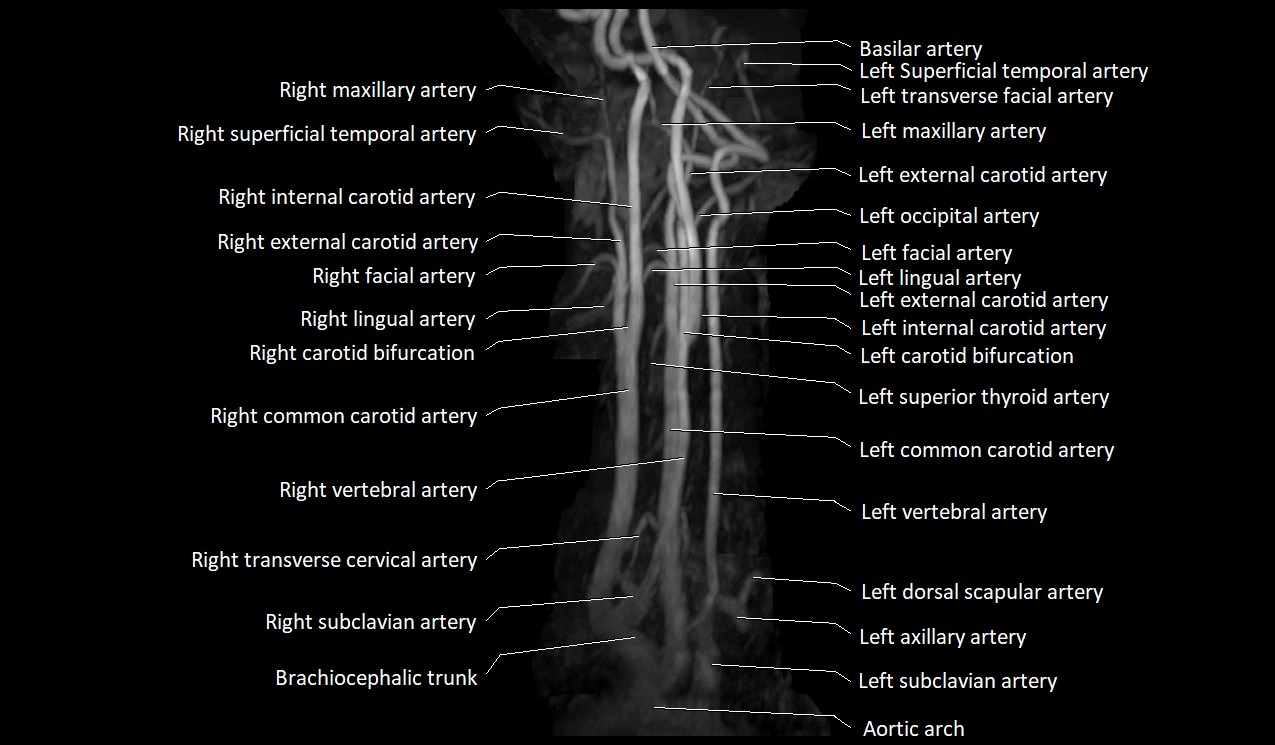

MRI images

image